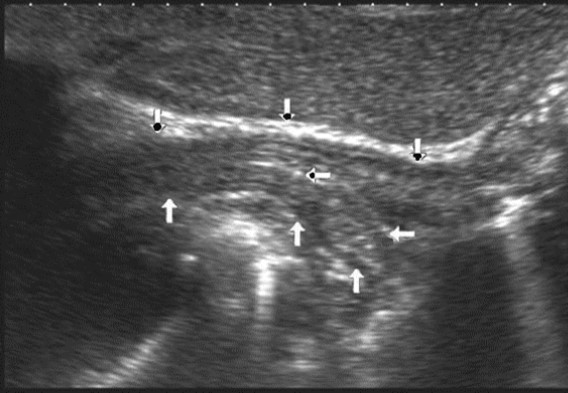

The polypoid type of gastric cancer was observed in 3 (4,9±2,8%) cases, the ulcerative type – in 18 (29,5±5,8%), the infiltrative ulcerative type – in 27 (44,3±6,4%) and the diffuse infiltrative type – in 13 (21,3%±5,2%) cases respectively (Table 2). On the echogram, the tumor was

Visualized as a polypoid formation on a wide base above the gastric mucosa of a non-uniform structure, an irregular surface (Figure 5, Figure 6, Figure 7).

Figure 5.The polypoid type of gastric carcinomas for T3 stage. On the posterior wall of the antrum, a polypoid formation with a fuzzy contour is visualized, the image of the mucous and serous membranes (arrows) is discontinuous.

Figure 6.The gastric carcinoma for T3 stage. The tumor is visualized as a polypoid formation on a wide base above the gastric mucosa of a non-uniform structure, an irregular surface (arrows).

T2 stage of diffuse carcinoma was recorded in 14 cases – among them 5 cases of ulcerating forms, 5 cases of infiltrative ulcerative forms and 4 cases of diffuse infiltrative forms. Gastroscopy diagnosis was established in all 10 cases of ulcerative and infiltrative ulcerative forms of gastric carcinomas and in 3 cases of diffuse infiltrative forms. Ultrasound diagnosis was established in 13 cases of diffuse carcinoma, except for one case where the location of the ulcerative form was in the fundus of the stomach (Figure 8, Figure 9, Figure 10).

Figure 8.Diffuse infiltrative form of the gastric carcinoma of stage T2 on the anterior wall of the stomach (arrows). The integrity of the mucous layer is not broken.

Figure 9.The gastric carcinoma of diffuse form. An area with a local thickening up to 5 mm, a length of about 37 mm, is visualized on the anterior wall of the stomach body. The left arrows show the differentiated intact wall layers, the right arrows – local thickening hypoechoic of the anterior wall. Mucous, muscular and serous membranes are differentiated.

Figure 10.The gastric carcinoma of diffuse infiltrative form. An area with a local thickening up to 1,7 cm, a length of 3,68 cm, is visualized on the anterior wall of the antrum (arrows). The thickening of the normal stomach wall is 0,34 cm.